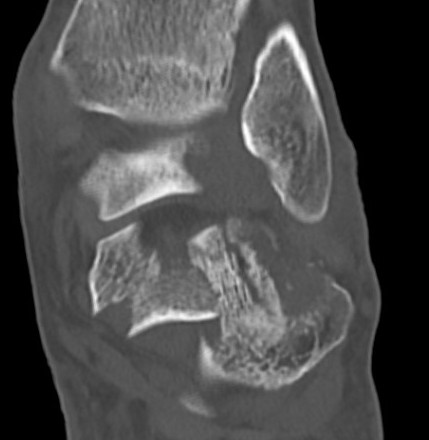

Sander I - non displaced

Sanders IV

Type III / IV Sanders